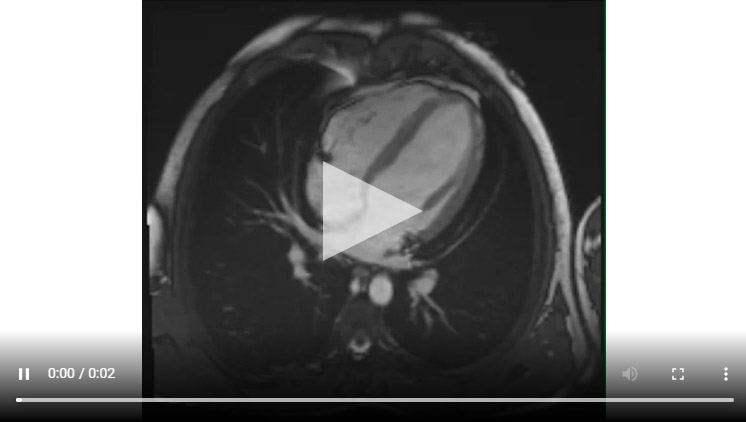

Figure 1A : Séquence Ciné-IRM coupe 4 cavités